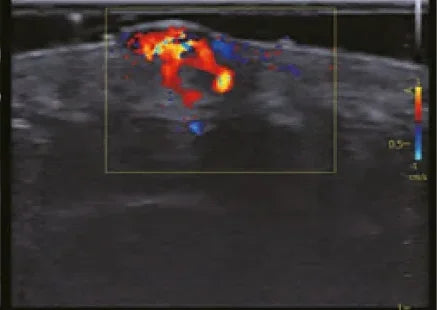

Mientras la ecografía común solo muestra imágenes de órganos y tejidos, el Doppler agrega una información valiosa: la velocidad, dirección y calidad del flujo sanguíneo. Eso significa que no solo vemos la “estructura”, sino también la “función”.

- Doppler color, que diferencia con colores la dirección de la sangre.